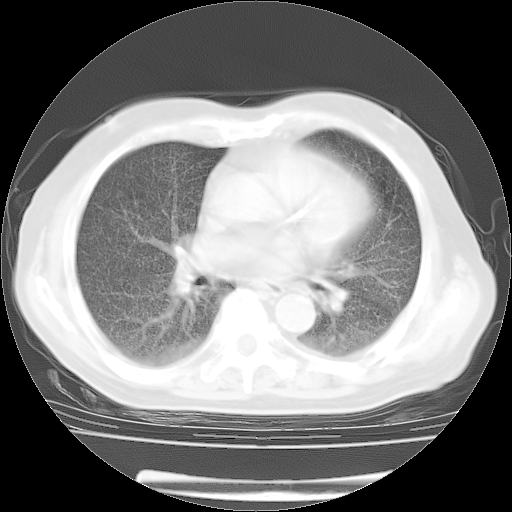

4月14日肺部CT

肺部CT平扫未见异常。